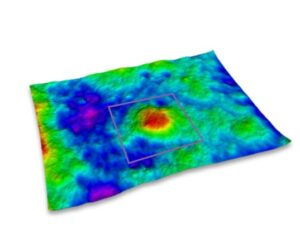

Vous pouvez également réaliser des acquisitions en 3D de la surface de la peau. Grâce à une technique appelée stéréo photométrique, le système C-Cube analyse plusieurs images dans différentes conditions d’éclairage. Le logiciel estime les normales de surface. Combiné à une calibration géométrique, il produit des informations d’élévation à chaque pixel.

Grâce à sa capacité unique de mesure de paramètres 3D, il est possible de mesurer l’élévation des boutons avec la hauteur du pic (Sp) et l’amplitude totale (Sz). Un effet du produit testé pourra être prouvé si l’élévation du pic diminue dans le temps.

Élévation des boutons Hauteur des pics et amplitude